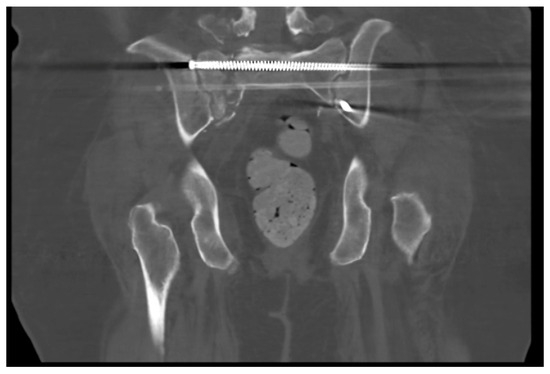

Figure 2.

A still image from an axial CT of the pelvis in a skeletally mature individual better demonstrating a vertical shear sacral fracture.